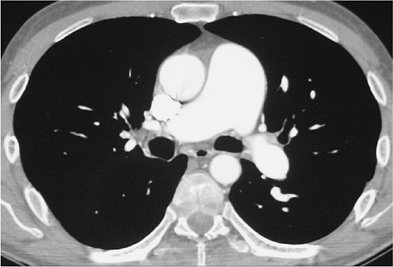

FIGURE 17-3. Acute PE. A: CTPA of a 77-year-old man with shortness of breath shows an intraluminal filling defect, surrounded by a rim of contrast, within the right lower lobe segmental pulmonary arteries (arrow). B: Coronal CTPA shows decreased caliber of arteries in the right lung compared with the left and filling defect within right lower lobe vessels. C: Catheter-based pulmonary angiogram confirms clot within right lower lobe vessels (arrows).